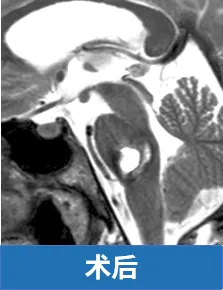

好在我是幸运的,巴特朗菲教授接下了我这场“悬崖边”的手术。他为我精细清除血肿及血管畸形的同时,特别注意保护脑桥后部实质及外展神经、面神经的完整性。

术后一年,明显可以看到我的面神经和外展神经功能已基本恢复,真正的、发自内心的笑。我终于回到了从前的样子,那种摇摇欲坠的恐惧,正在被稳稳踩在脚下的踏实感取代。我知道,是教授那双神奇的手,把几乎坠崖的我,一点点拉了回来。

上述真实案例及图片来自于INC巴特朗菲教授课程演讲。

桥脑海绵状血管瘤案例